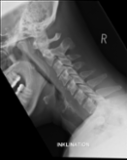

The severe cervical spine pain prompted an emergency MRI examination, which showed a clear prevertebral inflammatory soft tissue process. On close inspection, a calcific deposit anterior to the dens axis can already be suspected on MRI (especially T2 or axial T1fs Gd+). The calcium depot is only shown very fluffy on X-ray and CT, suggesting an acute stage with precipitation/resorption of the calcific milk.

The longus colli muscle is a less common location of this condition, which should be referred to as HADD or acute calcific deposit. Also affected may be supraspinatus tendon and other tendons of the rotator cuff, extensor carpi radialis tendon, deltoid muscle, or hip adductors.